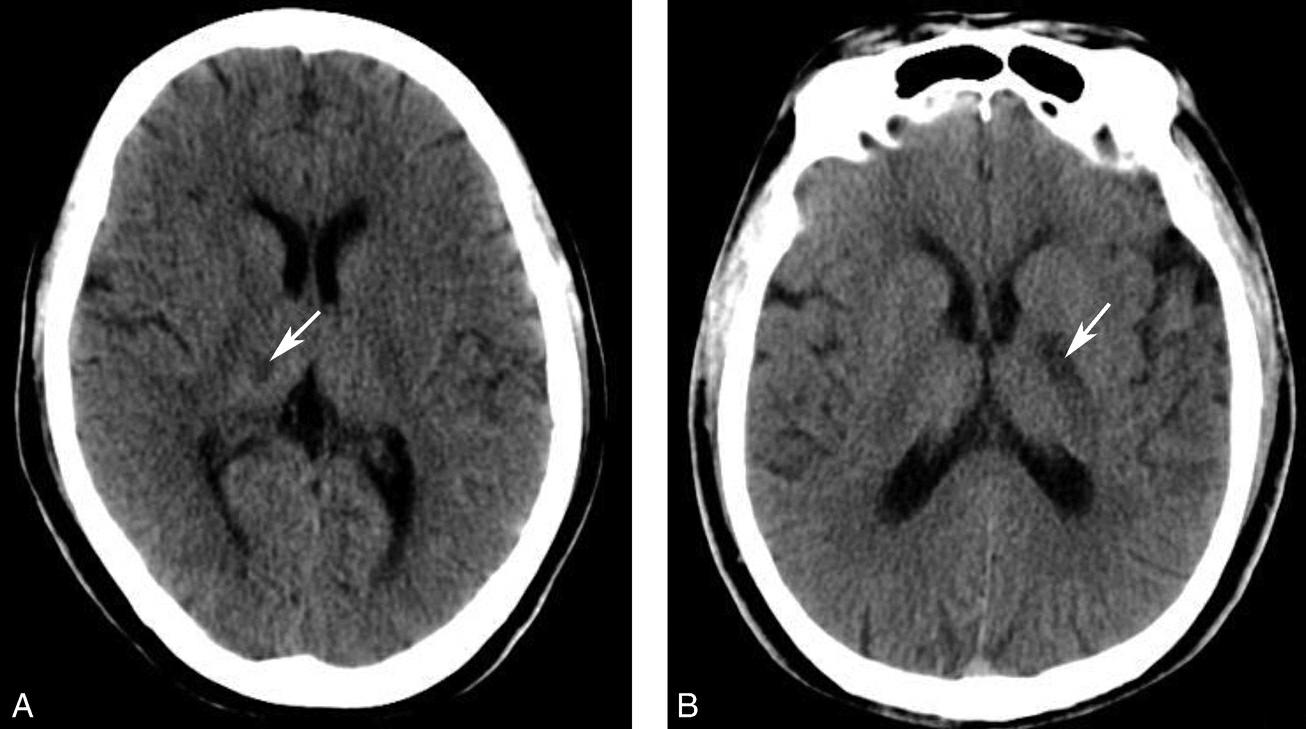

松果体、苍白球在成人期常出现钙化,属生理性钙化,一般无病理意义。需注意勿误诊为出血灶,尤其是单侧苍白球钙化时(图1-2-28)。

图1-2-28 苍白球生理性钙化

A.双侧苍白球对称性钙化,呈高密度影(箭);B.左侧苍白球钙化(箭),右侧苍白球钙化不明显